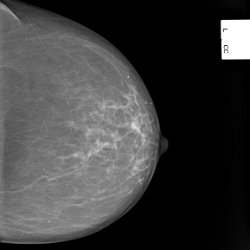

Mammografie